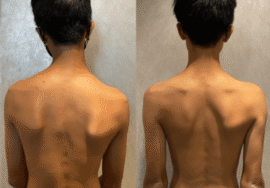

يُعد اعوجاج العمود الفقري عند المراهقين (الجنف) من أكثر مشكلات الظهر شيوعًا في فترة النمو. يظهر عادة في سن المراهقة دون سبب واضح. ومع ذلك، تشير الأبحاث الحديثة إلى أن المشكلة لا تتعلق فقط بشكل العمود الفقري، بل تمتد لتؤثر على توازن الجسم وطريقة تحكم المراهق في حركة رأسه ورقبته.

عند حدوث انحناء في العمود الفقري، يختل توازن العضلات والضغوط داخل الجسم. ومع مرور الوقت، قد تتأثر الإشارات العصبية القادمة من الرقبة إلى الدماغ. في هذه الحالة، يشعر المراهق أحيانًا بعدم التوازن أو يجد صعوبة في ضبط وضع رأسه، خاصة عند الوقوف أو الحركة لفترات طويلة.

أظهرت النتائج أن المراهقين المصابين بالجنف يعانون من ضعف في الإحساس بحركة الرقبة مقارنة بالأصحاء.

لاحظ الباحثون أن بعض المشاركين لم يتمكنوا من إعادة الرأس بدقة بعد تحريكه، وكانت الانحرافات في الوضعية أكبر من المعتاد.

كما وجدوا أن ضعف الإحساس يزداد مع ارتفاع درجة الانحناء في العمود الفقري، مما يشير إلى أن الاعوجاج قد يؤثر تدريجيًا على توازن الرأس والجسم معًا.